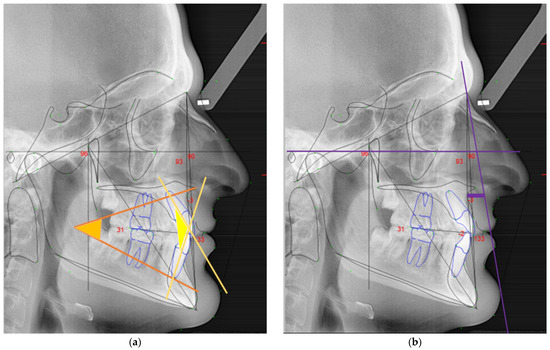

• Interincisal angle: angle found between the upper incisal axis and lower incisal axis (in yellow, Figure 2a);

• Lower facial angle: angle between the planes formed by the anterior nasal spine to Xi point (ANS-Xi) and the Xi point to protuberance menti (Xi-PM) (in orange, Figure 2a);

• Facial convexity: direct measurement parallel to the Frankfort plane between point A and facial plane (N-Pog) (in purple, Figure 2b);